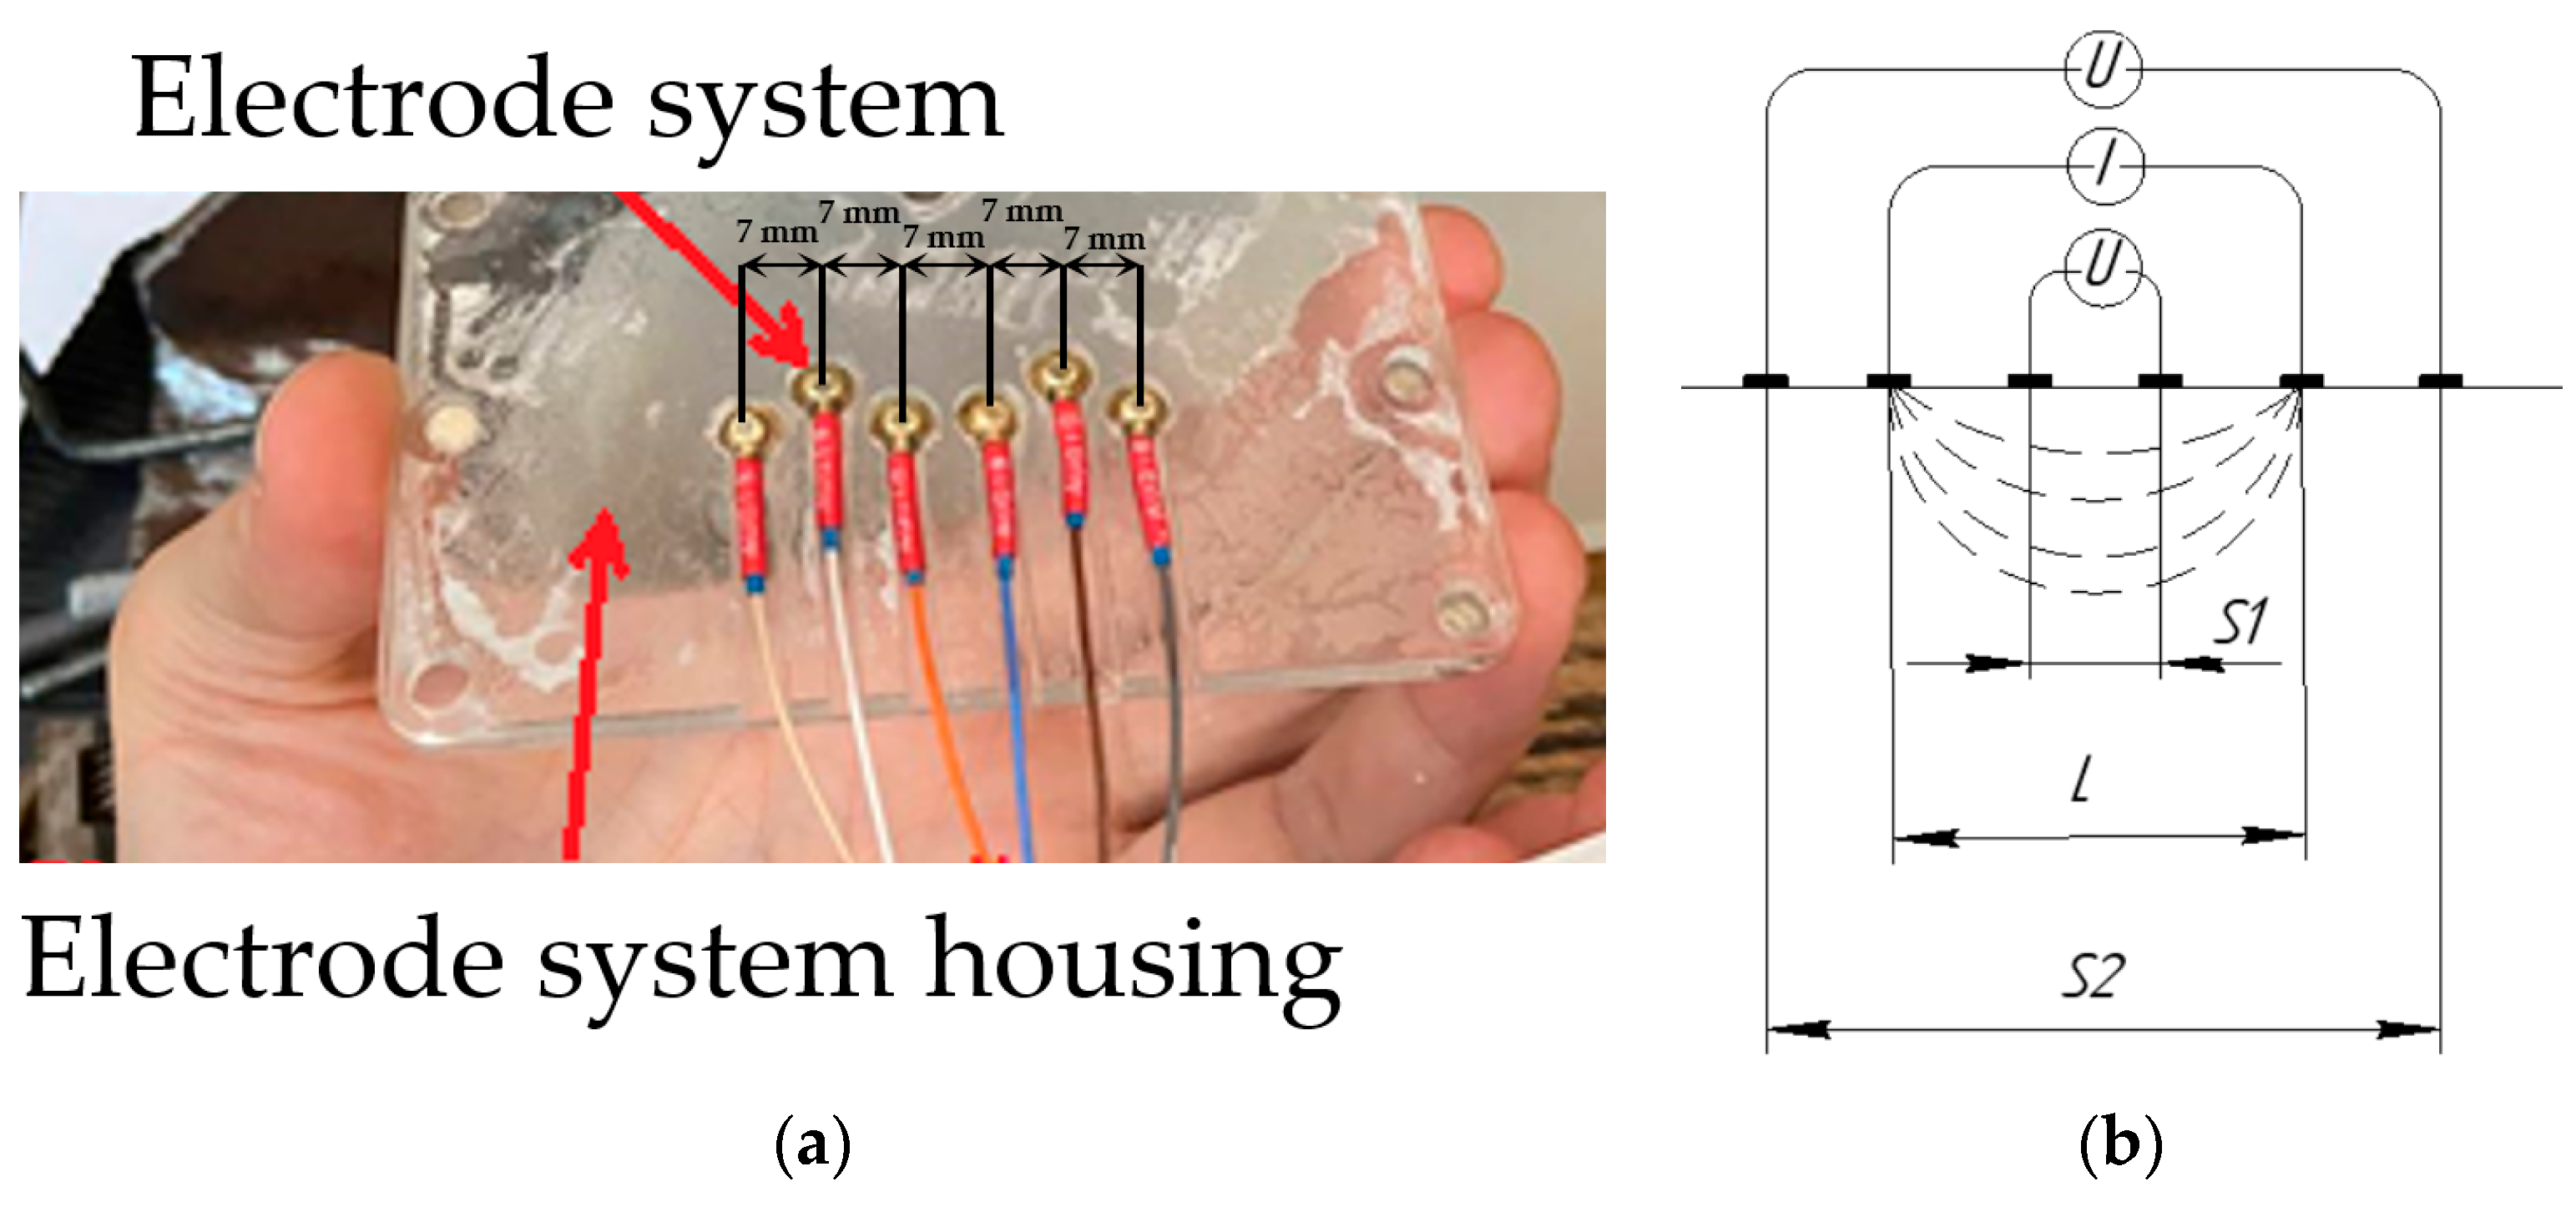

2.6. Measurement Design

3.2. Study of the Amplitude Parameters of the Electrical Impedance Myography Signal at Different Pressures of the Electrode System